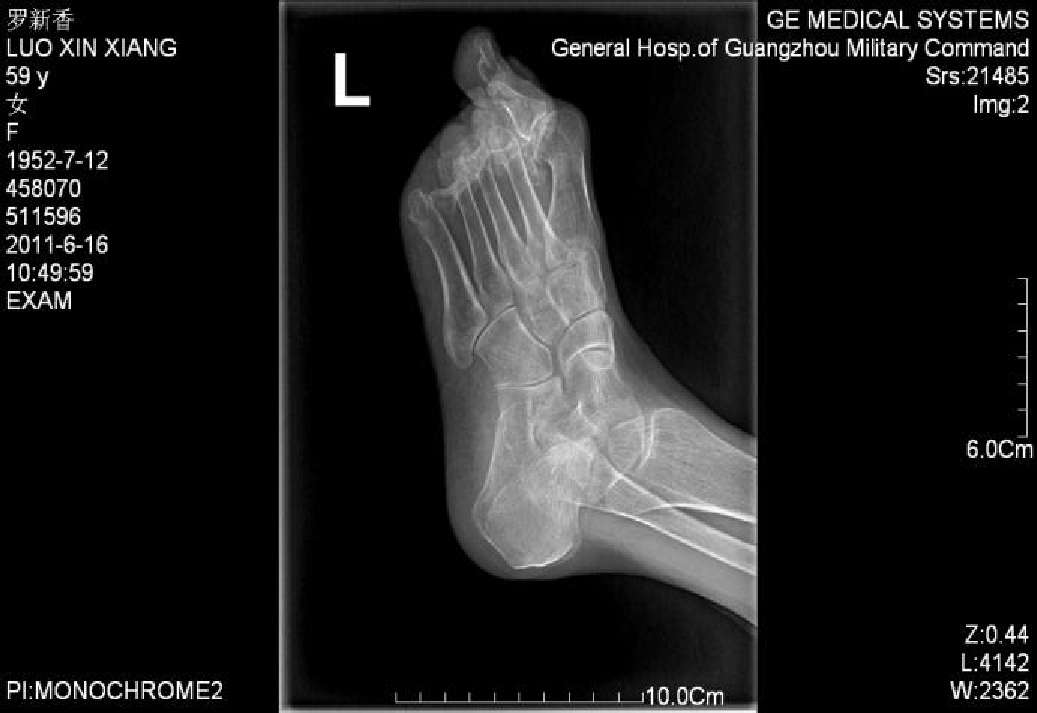

例4:罗XX,女,60Y。

左足:第1-5跖趾关节脱位,足拇外翻。

胼胝体:第一跖骨内侧,第2/3跖骨头跖侧,第5跖骨头跖/外侧。

左足:第2-5趾爪形趾。

术式:左足:第1跖趾关节融合+第2-5跖趾关节成形术;右足:第4趾间关节融合+第5跖趾关节成形术